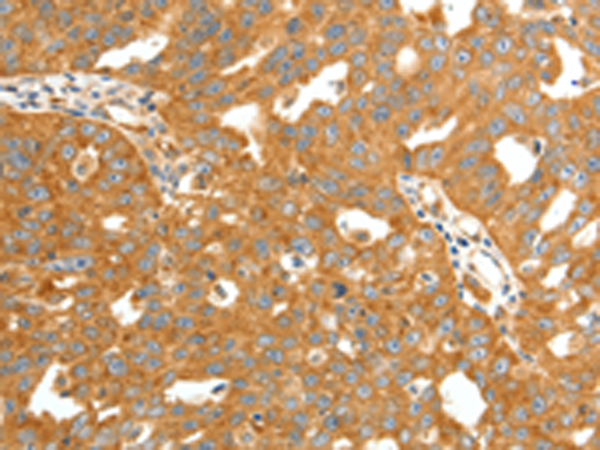

分类: 科研抗体货号: P11340别名:应用: IHC反应种属: Human, Mouse, Rat